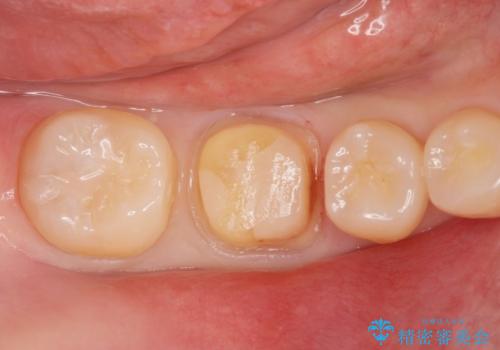

- 歯が欠けたとの事で来院。プラスチックの樹脂で治療されたところが欠けていて中に虫歯が再発していました。

古い樹脂と虫歯を拡大鏡下でしっかり取り除き、ジルコニアクラウンにて治療しました。